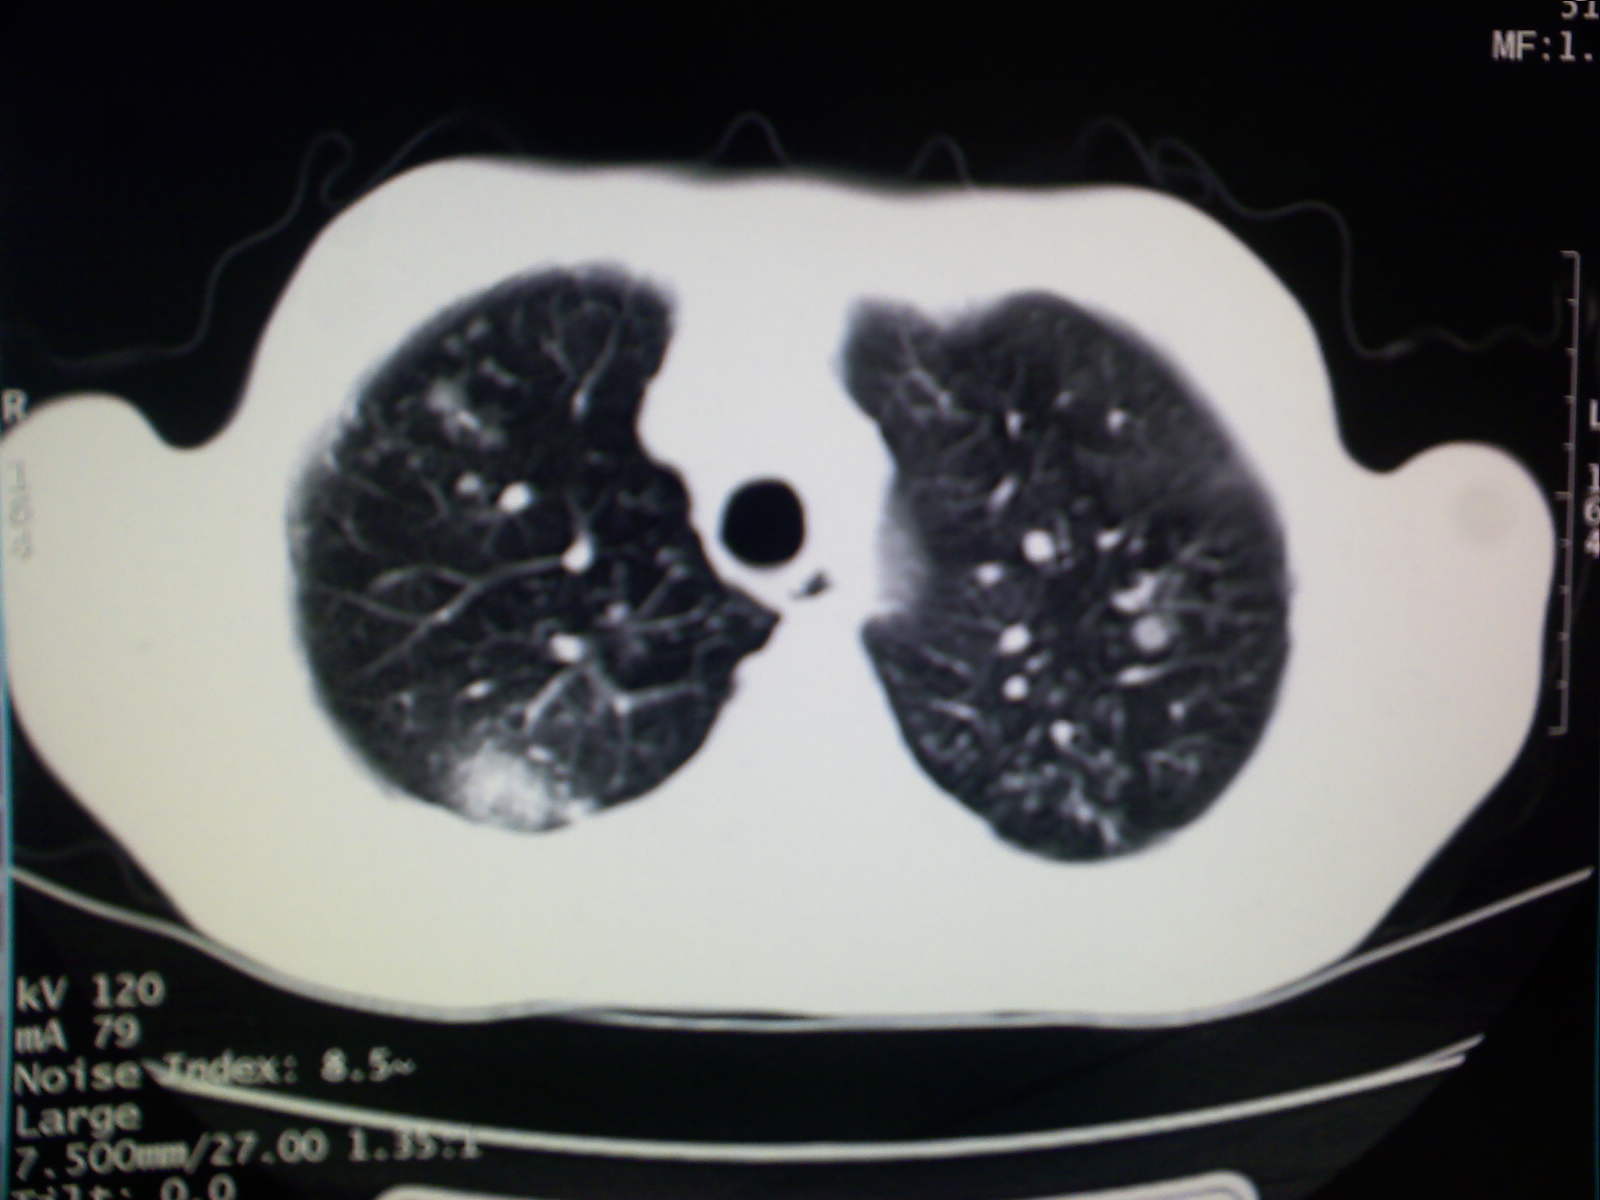

以下是引用卜一在2009-4-11 15:50:00的发言:[br]双肺继发性肺结核伴空洞形成,不排除合并霉菌感染!(病灶呈多形态 多特征 散在分布)。另:合并支气管扩张征伴感染!

以下是引用主力军在2009-4-11 15:55:00的发言:[br]两肺继发性肺结核可能性大。

以下是引用康鹏在2009-4-11 16:30:00的发言:[br]双肺继发性肺结核伴空洞形成合并感染[br]支气管扩张合并感染